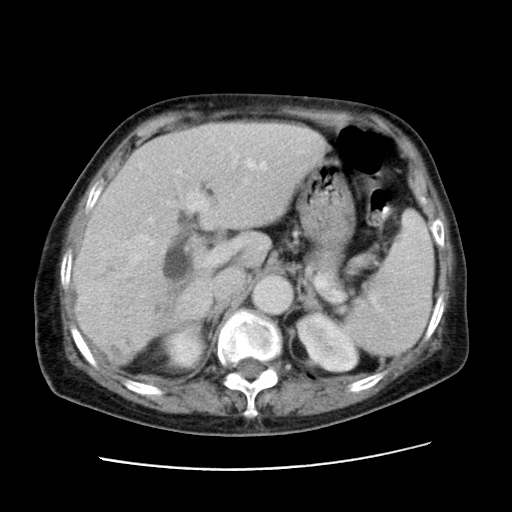

标题: CT25203:上腹部增强,看看

女,77.无不适

肝脏变异、异位胆囊,肝右叶肝内胆管结石并肝内胆管扩张。

肝右叶肝内胆管结石并肝内胆管扩张。

肝右叶肝内胆管结石并肝内胆管扩张。胆总管下段梗阻,考虑壶腹部占位。

右侧肝内胆管局限性扩张,其内密度不均匀,扩张的胆管壁增厚,考虑肝内胆管炎合并结石可能性大